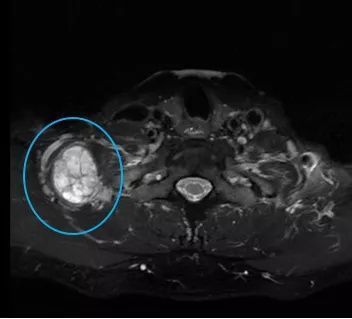

张先生和赵先生住院以后都做了颈部的磁共振检查,检查结果显示张先生的肿块长在了下颌角的边上,肿块还包绕着颈部的大血管。而赵先生的肿块是从臂丛神经上长出来的。

张先生颈部磁共振 医院供图

赵先生颈部磁共振 医院供图